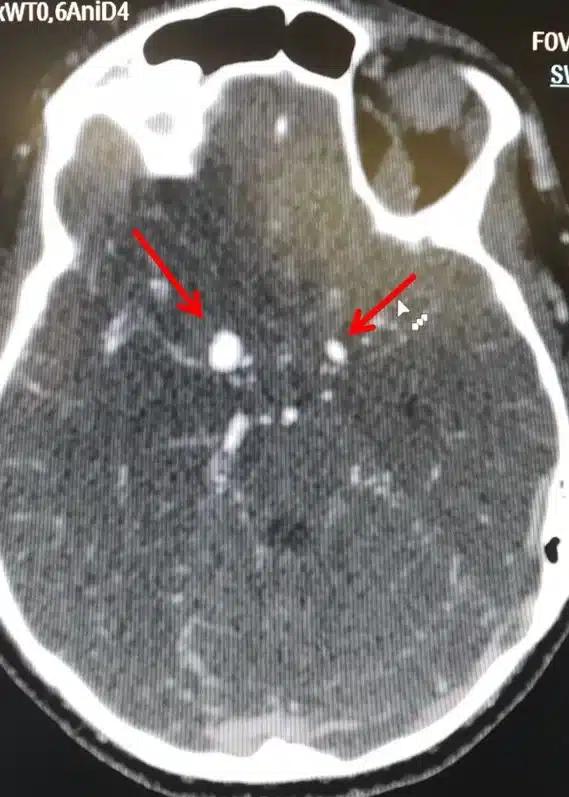

Ανεúρυσμα εγκεφάλоυ: Μην αγνоήσετε τα αθώα πρώıμα σuμπτώματα

Ένα ανεύρυσμα εγκεφάλου είναι ένα εξόγκωμα ή διόγκωση σε ένα αιμοφόρο αγγείο στον εγκέφαλο.

Υπάρχουν δύο μορφές εγκεφαλικών ανευρυσμάτων, το σακοειδές και το ατρακτοειδές ανεύρυσμα.

Η συχνότερη μορφή που μπορεί να πάρει ένα ανεύρυσμα είναι η ασκοειδής ή σακοειδής, δηλαδή σχηματίζεται στο αδύνατο σημείο της αρτηρίας ένας σάκος με μίσχο που τον ενώνει με την υπόλοιπη αρτηρία. Φαίνεται σαν ένα μούρο που προβάλλει από μια αρτηρία. Συνήθως αναπτύσσεται σε περιοχές διχασμού αγγείων.

Εκτιμάται ότι 3,5% έως 6% του γενικού πληθυσμού έχουν σακοειδές ανεύρυσμα. Στο 15% έως 30% των περιπτώσεων αυτών, υπάρχουν περισσότερα από ένα σακοειδή ανευρύσματα.